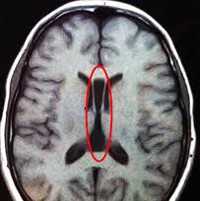

Одним из методов выявления пороков головного мозга у грудничков является нейросонография через родничок. Намного более точные данные у детей любого возраста и у взрослых получают при помощи МРТ головного мозга. МРТ позволяет определить характер и локализацию аномалии, размеры кист, гетеротопий и других аномальных участков, провести дифференциальную диагностику с гипоксическими, травматическими, опухолевыми, инфекционными поражениями мозга. Диагностика судорожного синдрома и подбор антиконвульсантной терапии осуществляется при помощи ЭЭГ, а также пролонгированного ЭЭГ-видеомониторинга. При наличии семейных случаев церебральных аномалий может быть полезна консультация генетика с проведением генеалогического исследования и ДНК-анализа. С целью выявления сочетанных аномалий проводится обследование соматических органов: УЗИ сердца, УЗИ брюшной полости, рентгенография органов грудной полости, УЗИ почек и пр.